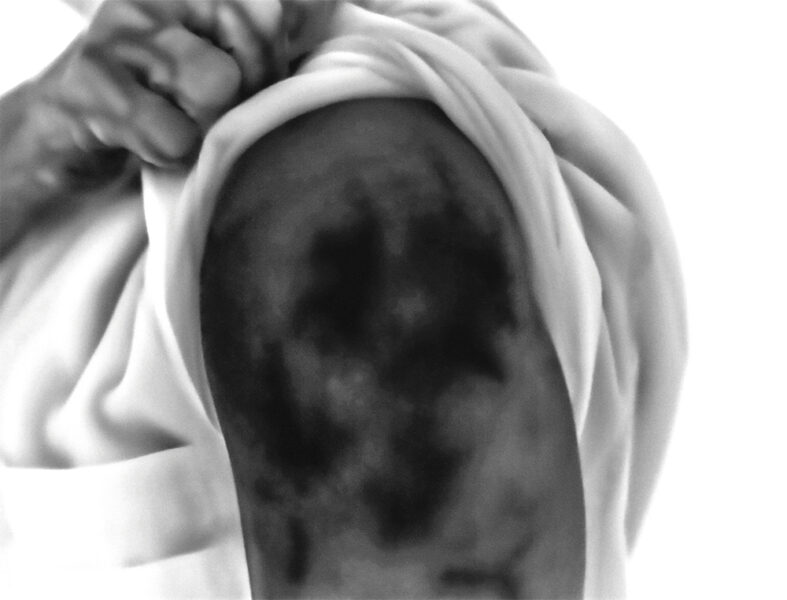

Injection Site addresses the politically charged global medical crisis of COVID-19. The project involved the use of a high-resolution thermal camera to photograph the arms of participants after vaccination. This has resulted in images over 130 participants, each image documenting and creating a visual trace of each person’s reaction to the vaccine. Rather than providing a simple scientific record, the ethereal images serve as evocative statements about individuality and our collective humanity. This project was intended to avoid being a polemic statement, but rather to cause pause for thought, to ignite conversation, and promote a mutual consideration for the actions and feeling of others, during a period when the health and wellbeing for all of us was such a contentious and divisive issue.